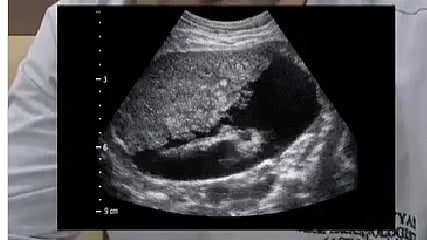

A preventive and diagnostic radiologist, Dr. Harsh Vyas, shared an ultrasound image of a 28-year-old man diagnosed with advanced and irreversible liver cirrhosis, even though the patient reportedly consumed alcohol only occasionally. The image and accompanying caption were posted to Dr. Vyas’s Instagram account on December 27, 2025, sparking public attention to liver disease risk factors.

In his social media post, Dr. Vyas explained that the ultrasound (USG) imaging revealed signs consistent with liver cirrhosis, a condition where healthy liver tissue is replaced by scar tissue (fibrosis) and the organ’s structure and function are significantly impaired. The scan also showed ascites, excess fluid accumulation in the abdominal cavity often seen in advanced liver disease and associated with complications such as pain and swelling.

Dr. Vyas noted that both he and the patient understood the condition had progressed to an advanced stage, and when the patient’s mother asked if her son would recover, he indicated that the disease was irreversible at this point and that a liver transplant might be the only applicable intervention.